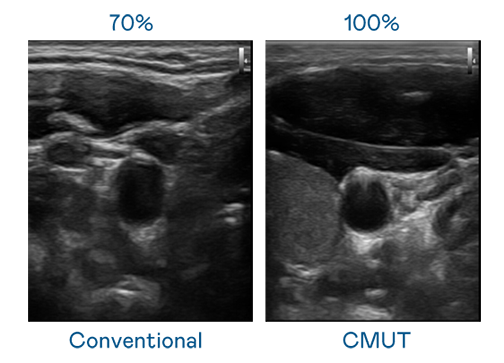

CMUT 技术是一种用电容式微机电元件来产生超音波讯号的技术。与传统 PZT 压电式技术相比,CMUT 频宽增加 30%,更宽频的超音波讯号让影像解析度大幅提升,是实现高影像品质医疗超音波扫描、促进精准医疗发展的关键技术。

大频宽带来超清晰影像

超音波影像的解析度高低,首先取决于探头能发出的讯号频宽。米兰体育 CMUT 可提供高清晰的超音波讯号,提供高频宽、高灵敏度、影像纹理细节更高的超音波影像,协助医护人员缩短影像判读时间及利用精准的医疗影像进行诊断。